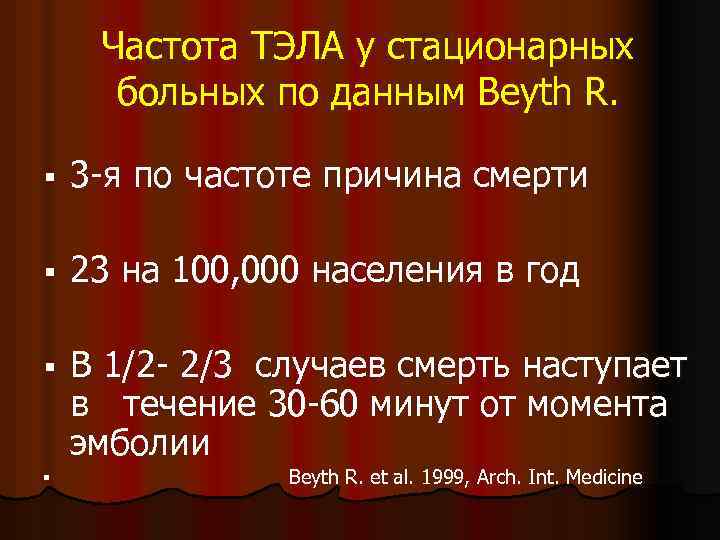

Частота ТЭЛА у стационарных больных по данным Beyth R. § 3 -я по частоте причина смерти § 23 на 100, 000 населения в год § В 1/2 - 2/3 случаев смерть наступает в течение 30 -60 минут от момента эмболии § Beyth R. et al. 1999, Arch. Int. Medicine